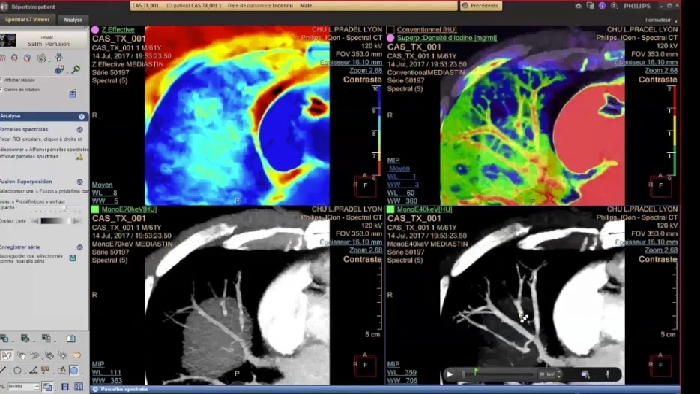

Les différentes cartographies spectrales les plus utilisées en routine

IQon Spectral CT est une nouvelle modalité scanner qui propose systématiquement plusieurs images conventionnelles et spectrales pour tout diagnostic. En routine, les cartes spectrales s’interprètent comme pour l’IRM par comparaison des différentes cartographies juxtaposées. Elles peuvent aussi être fusionnées les unes aux autres.

Les différentes cartographies

CT Conventionnel

IQon Spectral CT

• Le mode mono énergie ou les cartes MonoE virtuelles (en unités Hounsfield) simulent un faisceau à RX monochromatique de 40 à 200 keV où l’utilisateur pourra faire varier l’énergie de 40 à 200 keV à l’aide d’un simple curseur sur l’image. La carte basse énergie de 40 KeV rehausse le contraste tissulaire ou iodé (l’atténuation maximale de l’iode est à 33 keV) et peut être utile dans le dépistage des lésions hyper vasculaires. Ce mode permet de diminuer les volumes de contraste injecté pour tout examen artériel, par exemple de 20 à 30cc pour une aorte abdominale standard ou un TAVI)*.

• La carte de densité d’Iode est une carte où le bruit a été soustrait, qui met en évidence le signal de l’iode uniquement. Elle est très souvent utilisée en comparaison de la Carte MonoE à 40 keV et permet de d’évaluer l’absorption du produit de contraste par les tissus avec la possibilité de mesurer des concentrations d’iode via un ROI.

• La Carte VNC ou « virtuel sans contraste » permet de diminuer la dose en supprimant la série sans injection. Les informations sans contraste sont extraites de la série injectée en supprimant la carte de l’iode.

• La carte d’imagerie paramétrique Z-Effectif reflète le numéro atomique moyen (de chaque pixel) et peut indiquer par exemple des zones graisseuses au sein des tissus.